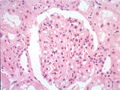

- ★(4)IgA nephropathy

Microscopic findings (HE, high power view): Slight expansion of the mesangium is noted (area within red dotted line).